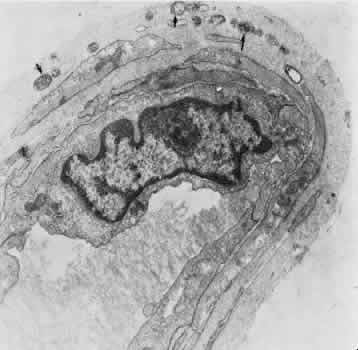

The iris blood vessels derive from the major iridic arterial circle and drain into the vortex system. The blood vessels of the iris are believed to have a slight corkscrew shape so they can accommodate to the changes in the length of the iris during dilation and contraction. A striking finding in all the iris vessels is the presence of thick collagenous adventitia that is several microns thick. There are approximately 200 radial vessels in the iris. The density of these vessels is greater than expected for the nutrition of the iris, and they probably account for anterior-segment thermal homeostasis and provide a high oxygen content for the corneal endothelium. Most of the vessels in the iris stoma are arterioles (Figs. 18, 19, and 20), venules, and capillaries (Fig. 21). The capillaries have unfenestrated endothelium with tight junctions. The main branches of these radial vessels form an incomplete circular arterial ring at the collarette (minor iris circle). Branches from the minor circle extend into the pupillary region to form capillary arcades. The venous drainage system parallels the arterial inflow pattern. The radial arteries of the iris are truly arterioles, with an overall diameter of 15 to 50 μm. The radial iridial veins are technically pericytic venules. They are approximately 30 to 90 μm in diameter. The media consists of one or two layers of pericytes. These cells make frequent contact with the endothelial cells but not with each other.

Fig. 18. Electron micrograph of a human iridial arteriole. The endothelial cell (E) is richly supplied with cellular organelles. In some areas (arrow), the smooth muscle cells (S) are in close contact with the endothelial cells.